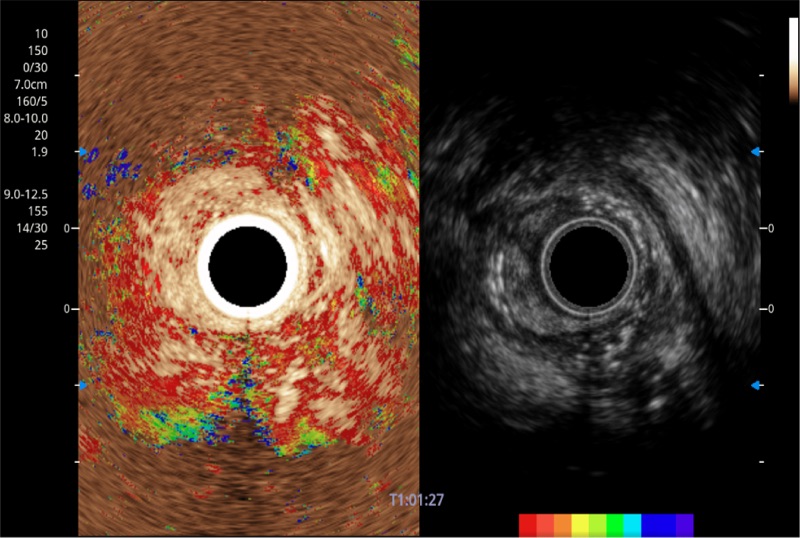

具有四种造影成像效果

肝左叶和肝静脉的横截面